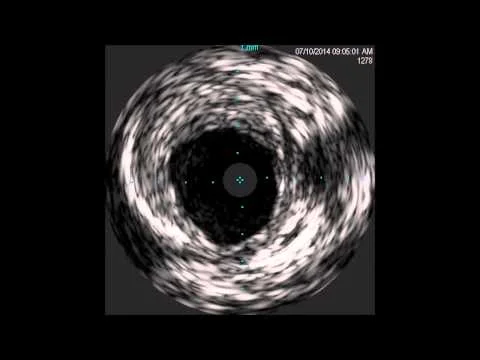

PTA and Infrared-X IVUS of Distal SFA/Popliteal In-Stent Occlusion